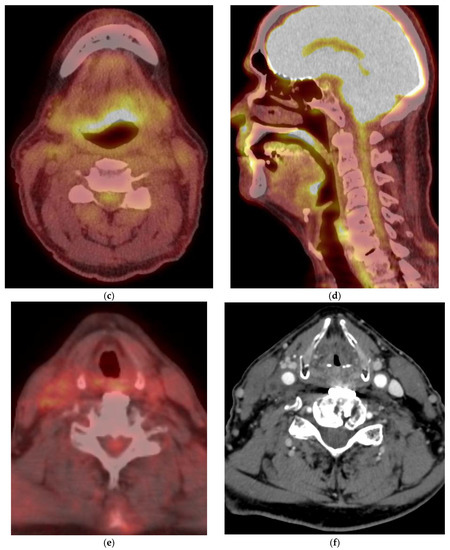

5. Imaging of Oropharyngeal Cancers

8.1. Initial Staging